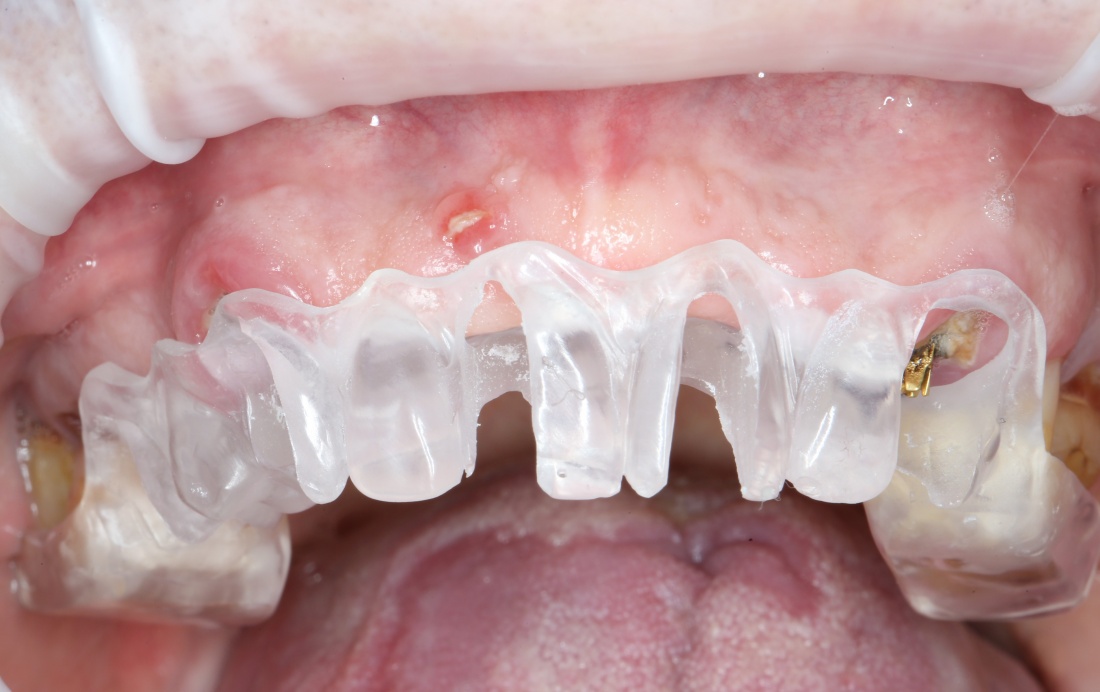

Рекомендации по установке имплантов. Для всех. Часть V.